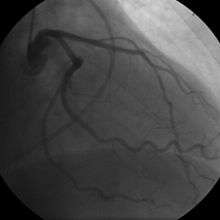

Coronary angiogram of a woman

For symptomatic patients, stress echocardiography can be used to make a diagnosis for obstructive coronary artery disease.[50] The use of echocardiography, stress cardiac imaging, and/or advanced non-invasive imaging is not recommended on individuals who are exhibiting no symptoms and are otherwise at low risk for developing coronary disease.[50][51]

The diagnosis of "Cardiac Syndrome X" - the rare coronary artery disease that is more common in women, as mentioned, an "exclusion" diagnosis. Therefore, usually the same tests are used as in any patient with the suspicion of coronary artery disease:

The diagnosis of coronary disease underlying particular symptoms depends largely on the nature of the symptoms. The first investigation is an electrocardiogram (ECG/EKG), both for "stable" angina and acute coronary syndrome. An X-ray of the chest and blood tests may be performed.

In "stable" angina, chest pain with typical features occurring at predictable levels of exertion, various forms of cardiac stress tests may be used to induce both symptoms and detect changes by way of electrocardiography (using an ECG), echocardiography (using ultrasound of the heart) or scintigraphy (using uptake of radionuclide by the heart muscle). If part of the heart seems to receive an insufficient blood supply, coronary angiography may be used to identify stenosis of the coronary arteries and suitability for angioplasty or bypass surgery.